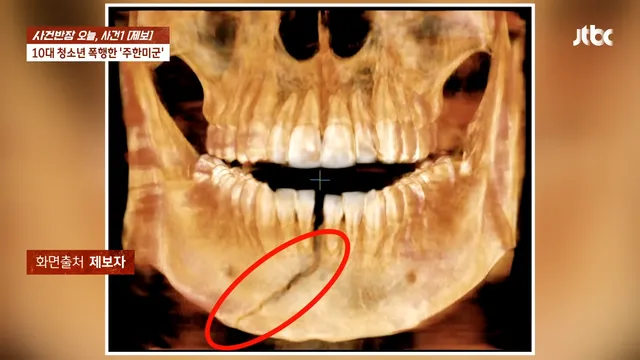

주한 미군 주먹에 10대 학생 ‘턱뼈’ 부서져

아니 어떻게 턱뼈가 저렇게 부셔지냐 ㄷㄷㄷ

턱뼈가 4군데 부러졌는데 의사도 사람이 때린게 맞냐며 의사하면서 주먹으로 이렇게 턱관절 골절된건 첨봤다고 함 ㄷㄷ